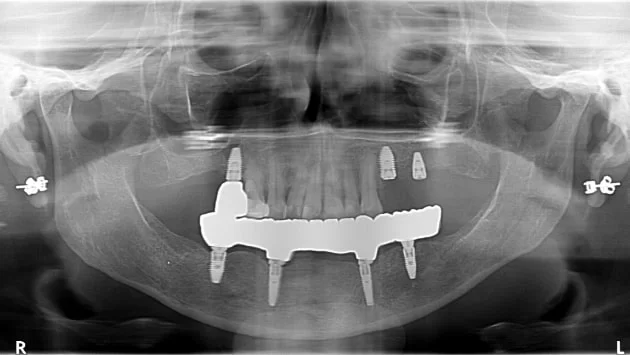

Si por alguna razón médica no puedes optar por el tratamiento All on 4, los implantes 3 on 6 pueden ser una excelente alternativa. Es una de las mejores opciones para una restauración total de la boca. Este procedimiento consiste en colocar 3 puentes de zirconia, cada uno sostenido por 2 implantes, para un total de 6 implantes.

Los implantes de zirconia que ofrecemos en Tijuana tienen una apariencia muy natural, son cómodos y mucho más accesibles que otros tratamientos. Si buscas una opción moderna y duradera en lugar de las dentaduras removibles tradicionales, los implantes 3 on 6 de X Dentistry son ideales para ti.